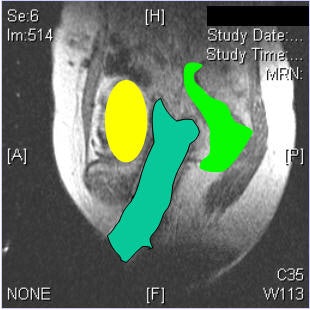

| No inadvertent insertion of interstitial catheter into bladder or rectum noted on CT (below) after MR (above). |

The patients' legs were then brought down and they were reimaged for the CT simulation. "We learned that it was very important to image with the legs down. There was substantial movement with the legs down. But once we figured that out, we were able to perfectly reconstruct the images so that the catheters lined up on MR," Viswanathan said.

The results showed that protection of the bladder and rectum was achieved. In all 10 cases, there was no inadvertent insertion.